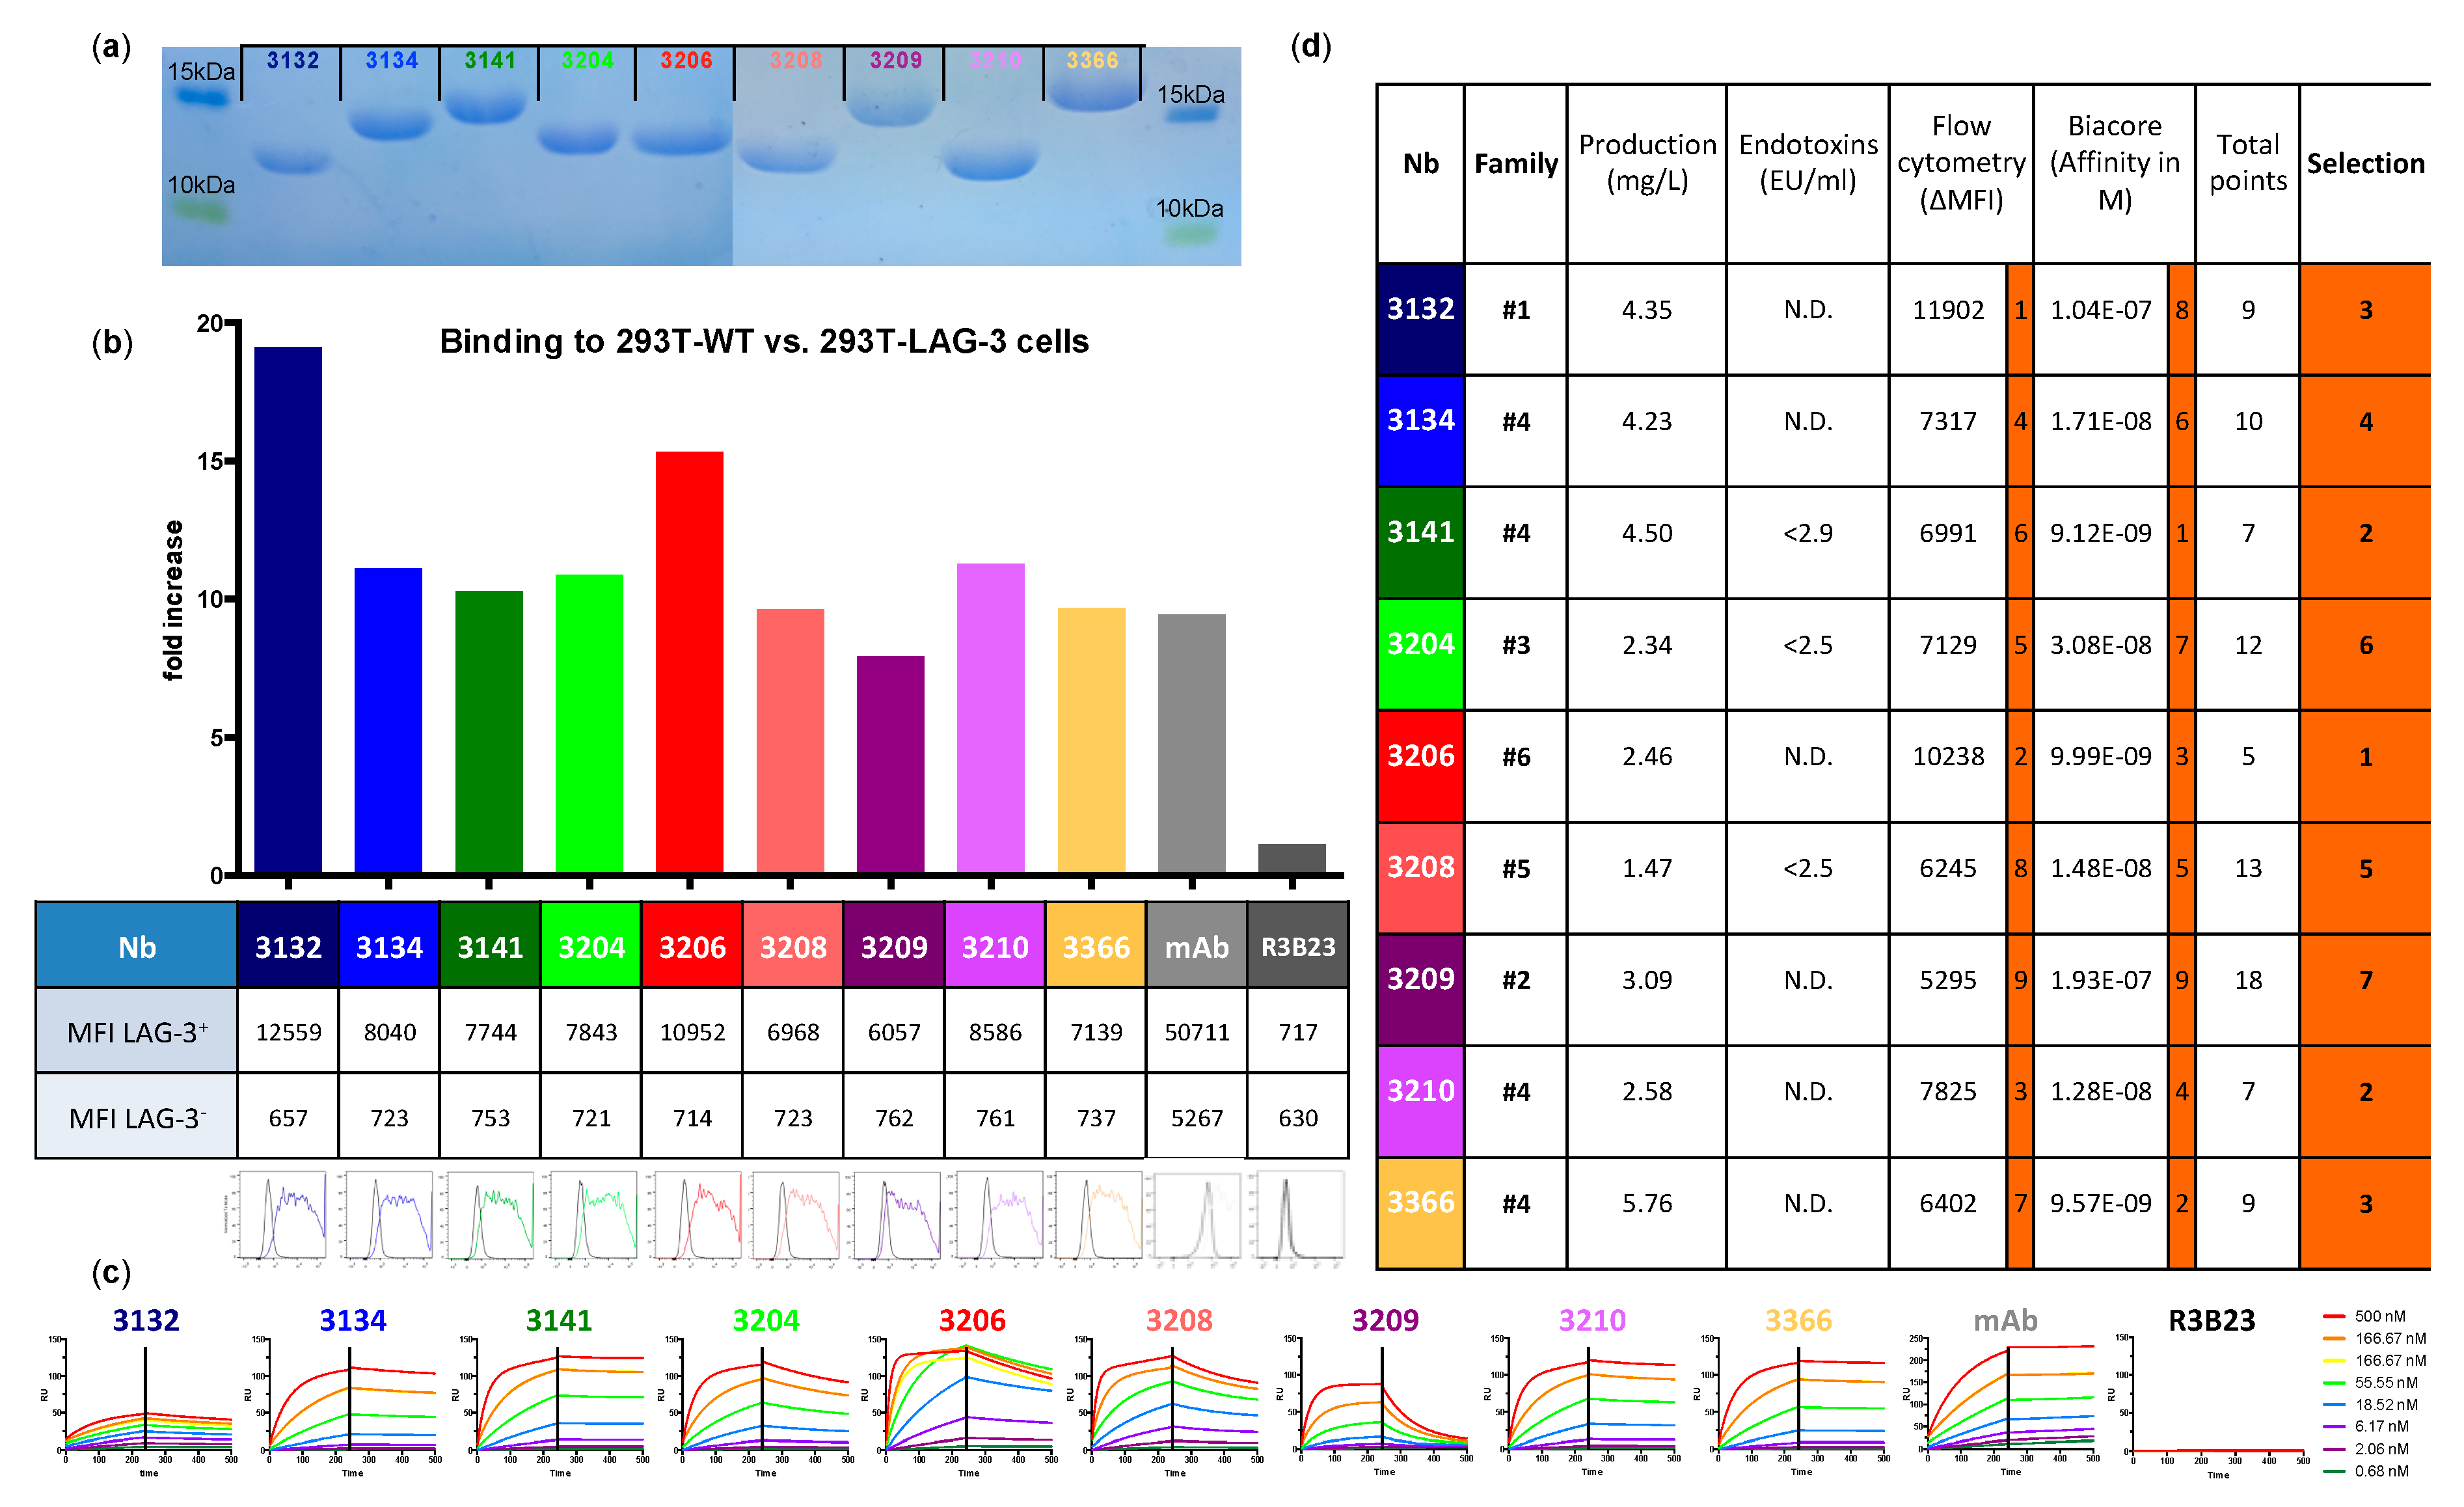

These results encourage the development of Nbs for molecular imaging of the inhibitory immune checkpoint receptor LAG-3. As this requires substantial preclinical evaluation, we developed and validated Nbs targeting mouse LAG-3 (moLAG-3) as probes for SPECT imaging. After alpaca immunization and biopanning via phage display, 114 Nbs were identified to bind recombinant LAG-3 protein. Bacterial extracts of these Nbs were further analyzed for binding to moLAG-3 using ELISA, flow cytometry and off-rate analysis using surface plasmon resonance (SPR). As such, nine moLAG-3 binding Nbs were selected. These Nbs were bacterially produced and purified, tested in flow cytometry, and their affinity was analyzed using SPR. Next, we labeled them with 99mTc, after which the biodistribution was assessed in immunocompetent and moLAG-3 gene-deficient mice by SPECT/CT imaging and dissection analyses. Subsequently, we evaluated the specific targeting of these Nbs in mice harboring tumors modified to overexpress mouse LAG-3.

2.4. Evaluation of Affinity/Kinetics

The affinity for moLAG-3 of purified Nbs and the off-rate of Nbs in periplasmic extracts was performed using a Biacore T200 device (GE Healthcare, Machelen, Belgium). The measurements were performed at 25 °C using Hepes-buffered saline (HBS; 0.01 M HEPES pH 7.4, 0.15 M NaCl, 3 mM EDTA, 0.005% Tween 20) as running buffer. Briefly, recombinant, moLAG-3 protein was diluted to 10 μg/mL in 10 mM Na-acetate pH 5.5 and immobilized on a CM5 sensor chip using linkage chemistry with 1-(3-(dimethylamino)propyl)-3-ethylcarbodi-imide (EDC) and N-hydroxy-succinimide (NHS). Free EDC-NHS linkers present on the chip were neutralized with 1 M elthanolamine-HCl pH 8.5. Three dilutions of periplasmic extracts and seven dilutions of purified Nbs were analyzed at a flow rate of 10 µL/min. The association was set to 240 s and the dissociation to 300 s for each dilution. After each cycle, the chip was regenerated twice for 30 s using 100 mM Glycine HCl pH2.0. The measured response units from the flow channel on which moLAG-3 protein was immobilized was subtracted from the response units measured on a flow channel without protein. Additionally, the signal from the blank (HBS only) was subtracted from each measurement. As a result, the off-rate value koff for Nbs in periplasmic extracts and the equilibrium dissociation constant KD for purified Nbs were calculated using the Biacore T200 evaluation software (GE Healthcare, Machelen, Belgium).